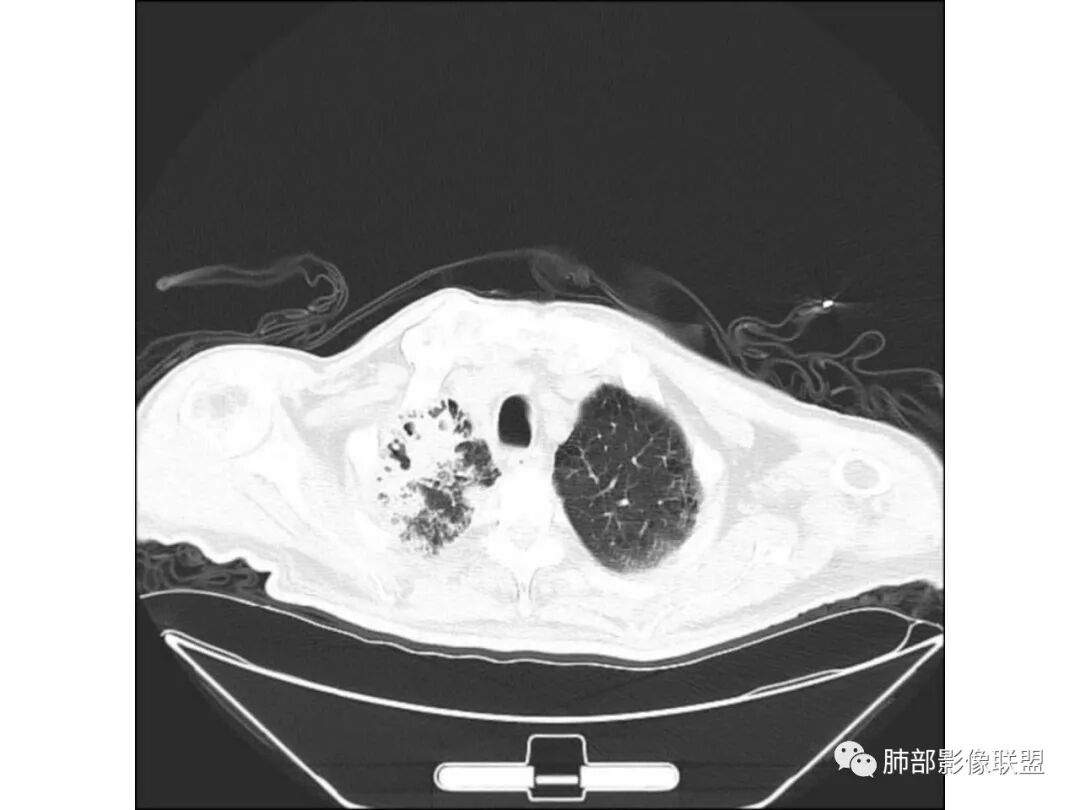

右肺上叶大片实变,其内可见虫蚀样空洞及扩张支气管,其中一空洞内可见曲菌球样结构,右肺体积略缩小。老年糖尿病患者,慢阻肺背景,考虑右肺上叶干酪性肺炎并曲霉感染。

老年男性,糖尿病患者,右上肺大片实变,内可见多发虫蚀样空洞,右尖段近胸膜处一空洞内可见一类圆形结节影,支气管扩张,淋巴结肿大,双下肺索条,胸膜增厚。结合糖尿病病史,首选考虑结核干酪性肺炎合并曲霉菌感染,待排肺炎型肺癌

老年男性,糖尿病基础,有咳嗽,喘累症状,病程10天,右上肺大片实变,内虫嗜样,无壁空洞,支气管壁增厚,扩张,淋巴结肿大,胸膜增厚,考虑干酪性肺炎,鉴别粘液腺癌。

老年男性,有糖尿病史,右肺上叶大片实变影,有支气管充气征,支气管走行僵直,有扩张,有多发无壁小空洞和俩个稍大空洞,胸膜稍增厚,双下肺野间质性改变,考虑肺结核,干酪性肺炎可能性大。

老年男性,右肺上叶大片实变,边界局部清楚,局部模糊,其内见支气管充气征及多发大小不等的小泡状及分枝状无壁空洞。双肺下叶磨玻璃样间质性改变。综合考虑右肺上叶结核,干酪性肺炎可能。

老年男性,糖尿病10年,咳嗽气喘10天,肺气肿背景,右上肺大片实变影,内见虫蚀样空洞及空气支气管征,局部可见新月形空洞影,支气管局部欠光整,考虑感染性病变,结核?其内合并曲霉可能。

老年男性,有糖尿病病史,右侧胸廓塌陷,肺容积缩小,右肺上叶片状实变密度影及高密度影,边缘模糊,内可见支气管充气征及多发虫蚀样空洞,考虑结核可能大。肝脏只有一层,看上去正常